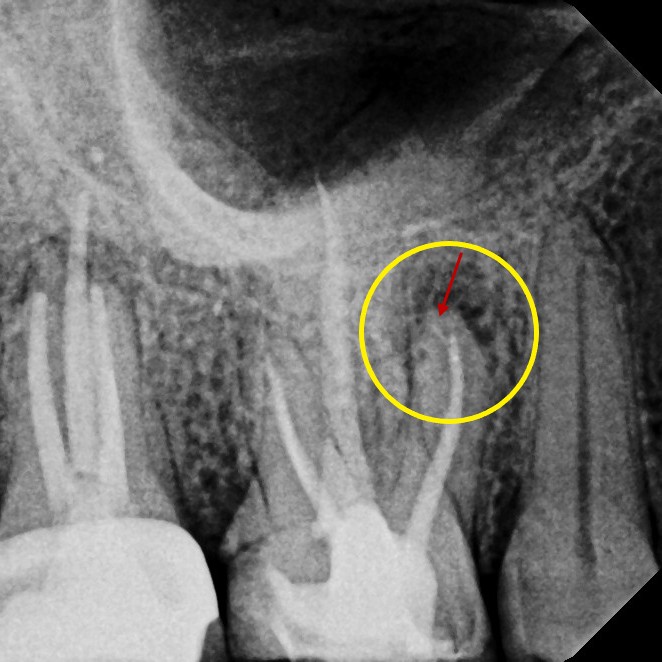

Retreatment

Sometimes, a tooth that has already undergone root canal therapy may not heal as expected or may develop new problems months or even years later. In these cases, endodontic retreatment offers a second chance to save the tooth. During this procedure, the existing filling materials are carefully removed from the canals, the inside of the tooth is cleaned again, and any hidden or untreated areas are addressed before the canals are sealed once more. This process allows your dentist to correct any issues and give the tooth the best possible chance for long-term success.

Thanks to modern tools and techniques, retreatment is a precise and effective procedure that can often be completed comfortably under local anesthesia. Many patients are surprised to learn that retreatment is no more uncomfortable than the original root canal. By choosing retreatment instead of extraction, you preserve your natural tooth, maintain your smile's appearance, and avoid the more complex and costly process of replacing a missing tooth.